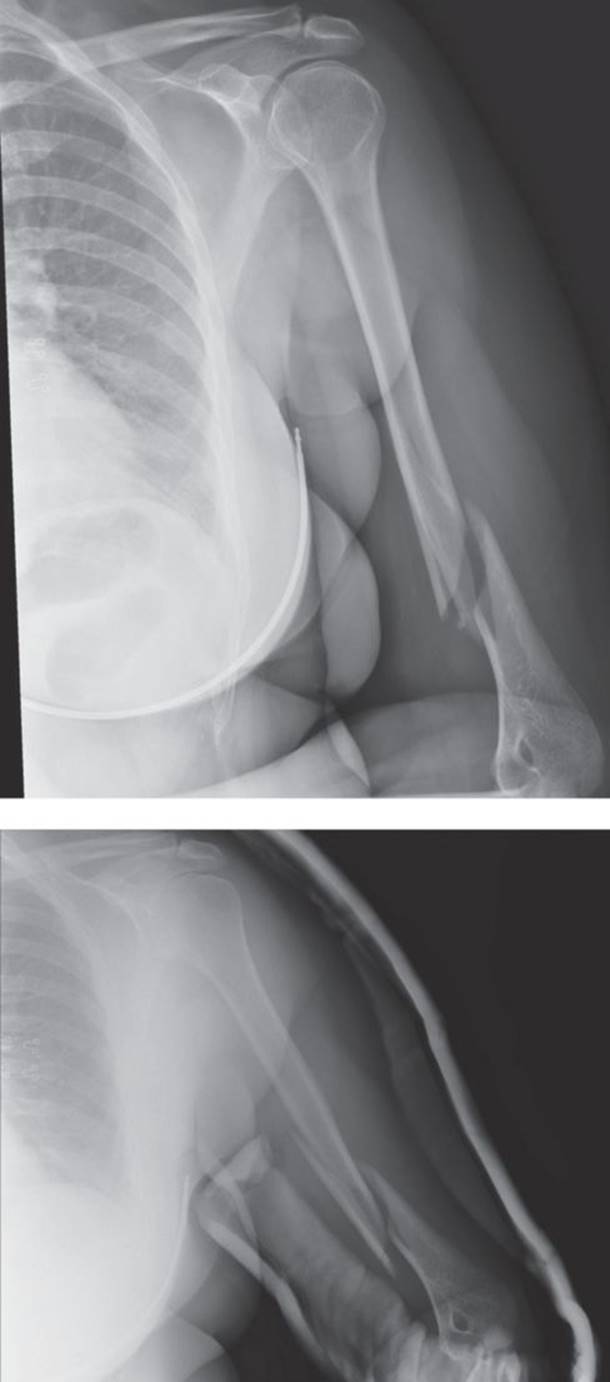

· More than 80% of proximal humerus fractures are non-displaced (Figure 2.6) or minimally displaced and do not require surgery

Figure 2.6 Non-displaced proximal humerus fracture. (Reproduced with permission of the Department of Emergency Medicine, Feinberg School of Medicine, Northwestern University.)